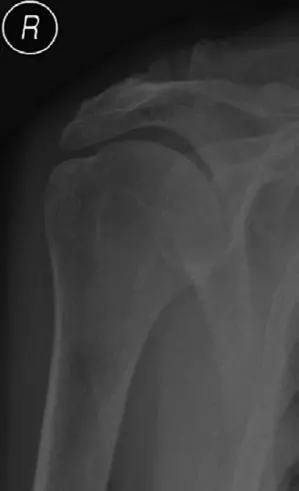

• الأشعة السينية (X-rays): هي الفحص الأولي والأكثر شيوعًا لتقييم المرفق. تكشف عن:

• الكسور (كسور العضد، الزند، الكعبرة، الناتئ المنقاري، اللقمتين).

• الخلوع.

• علامات التهاب المفاصل (تضيق المسافة المفصلية، نتوءات عظمية).

• التكلس العظمي المغاير (HO).

• تجزؤ العظم في حالات التهاب العظم والغضروف السالخ (OCD).

• في الأطفال، تساعد في التمييز بين الكسور واللوحات النموية الطبيعية (مثل نتوء المرفق).